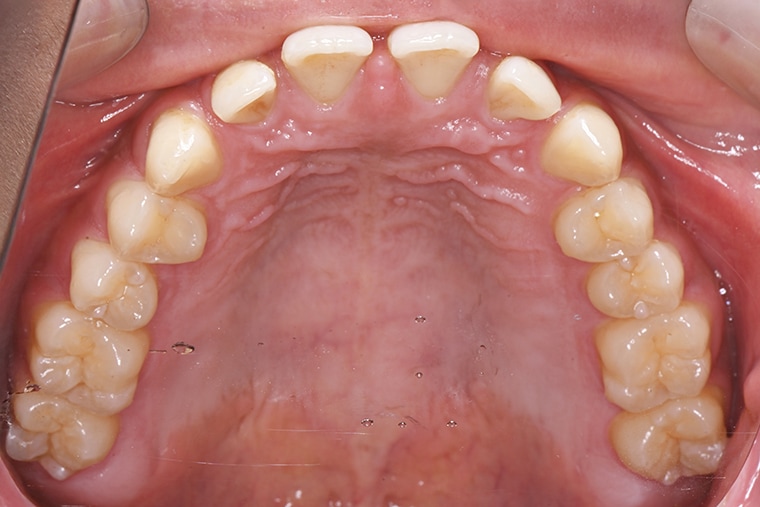

Case Study18歳男性すきっ歯のマウスピース矯正-矯正期間6ヶ月(2024年8月開始)